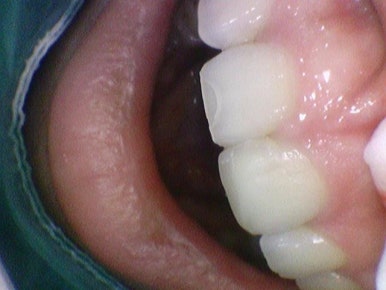

크라운과 라미네이트 중 라미네이트를 하기로 한 이유는 오른쪽 사진처럼

치아 뒤쪽에 교정이 끝나고 유지장치가 붙어있는 상태였기 때문에 크라운을 하는 경우 크라운에 유지장치가 잘 붙지 않을 뿐더러, 크라운을 하면 크라운을 하고 다시 새로운 유지장치를 재제작해야하기 떄문에

유지장치가 있는 부위는 크게 건드리지 않고 치아 앞쪽만 처리해서 붙일 수 있는 라미네이트를 하기로 하였습니다.